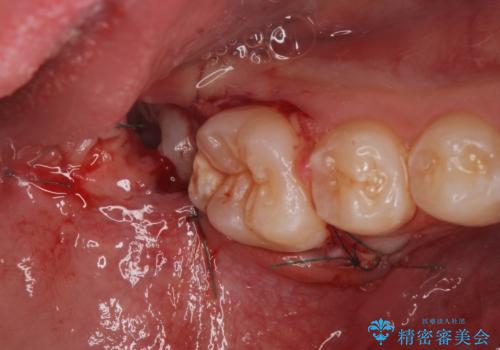

大きく歯が欠けた。 外科処置を行ったセラミック治療

歯冠長延長術をおこなったアプローチの難しい虫歯治療

外科処置の注意事項(リスク・副作用など)

- 外科手術のため、術後に出血、痛みや腫れ、違和感を伴います

- 口腔内の状態によっては適応できないことがあります